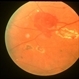

- Condition/keywords

- retinal capillary hemangioma, feeder vessel

- Fundus photo of a retinal capillary hemangioma after treatment of the feeder vessel.